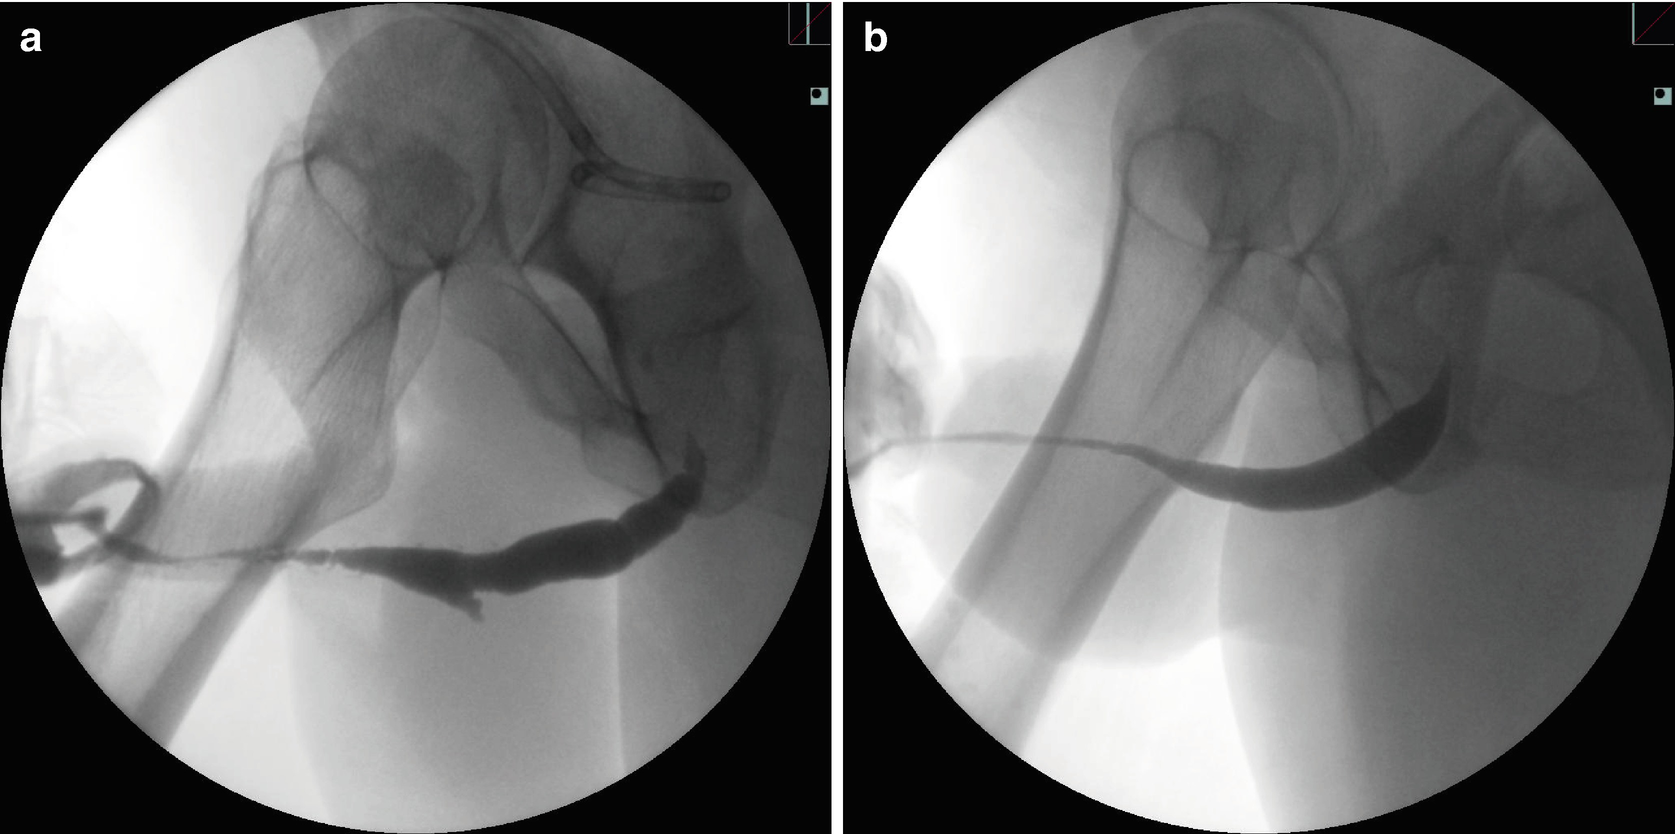

Penile urethral stricture related to: (a) multiple prior surgical procedures for penoscrotal hypospadias and subsequent complications, (b) lichen sclerosis (LS)